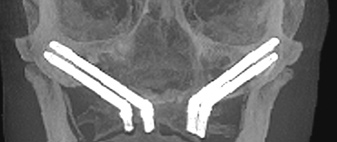

For patients who have zone 1 and zone 2 bone but lack zone 3 bone secondary to large pneumatized maxillary sinuses, inclining the implants posteriorly along the anterior wall of the maxillary sinus may enable an adequate anterior and posterior distribution of implants to support a fixed restoration while avoiding the need for grafting (Figure 6).4,10-15 Use of inclined implants also has been shown to be successful with immediate-loading procedures of the completely edentulous maxilla.5,13,15

Fig 6. Tilted posterior and traditional anterior implants, with presence of bone in zones 1 and 2 only.

Figure 6